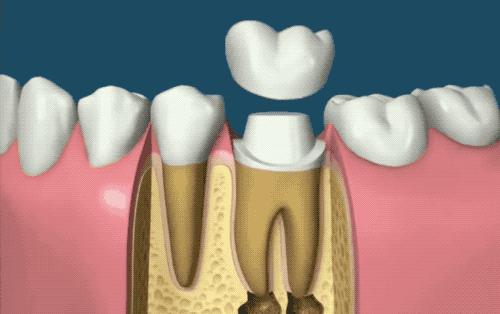

戴上牙冠

为了避免辛辛苦苦封闭好的牙齿因为咀嚼而裂开,牙医通常推荐给牙齿套上牙冠。这就是根管治疗最贵的地方!很多地方的医保中,拔牙、洗牙、补牙等治疗手段都是报销的,但材料填充物、牙冠都是不报销的...也就是说让牙齿部分变少的都报销,变多的都不报。牙冠有多贵呢?就是贵到哭啊...大概我这一口牙不出问题,奥迪的小兄弟奥拓应该已经开上很多年了...

根管治疗后,牙齿的炎症也会逐渐消失,牙齿也就被「半保留」下来了,不用像以前一样整颗牙都被拔掉。虽说治疗过程痛苦,但这种除去糟粕,留下精华的治疗方式,长期来说对于我们口腔健康是更有利的,也就成了现代牙体治疗中普遍的常规操作了。